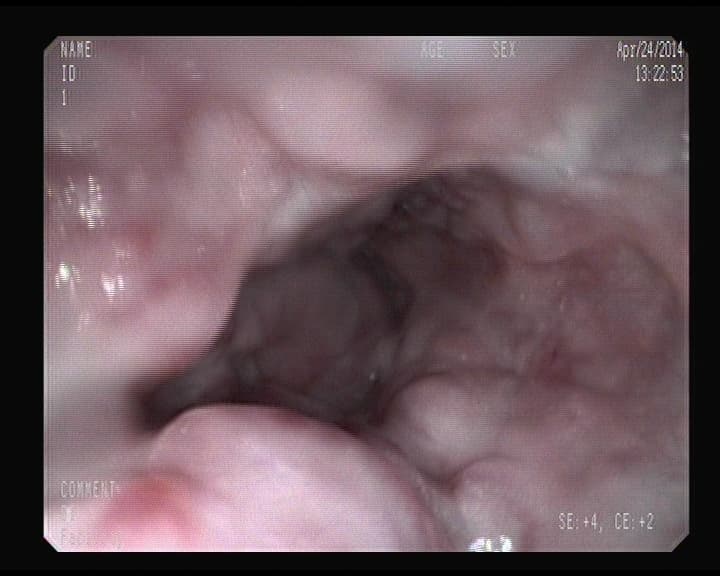

Otra cara de un orificio apendicular normal

Orificio apendicular visto desde el intestino grueso, sin signos inflamatorios.

Visión del orificio apendicular en ciego.

Ese orificio oscuro, es la entrada del apéndice.